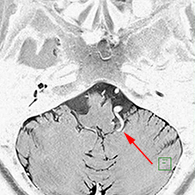

<画像所見>

左後下小脳動脈が左舌咽神経を圧迫していたために左咽頭部を中心に激しい痛みが生じていた。